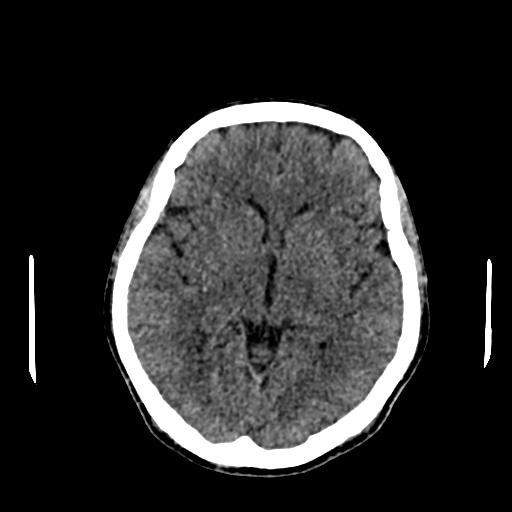

All other blood investigations including thyroid function tests and autoimmune screening were within normal limits. Plain computed tomography (CT) brain was done and revealed well-defined hypodensities seen in right lentiform nucleus chronic infarct.1 Otherwise, no intracranial haemorrhage and no acute ischemic infarcts seen at other areas. Brain magnetic resonance angiography (MRA) was ordered and it showed impingement of V4 vertebral artery to anterior lower pons near midline which is the exit of the left abducens nerve from the pons and also trigeminal nerve (blue arrow) and right abducens nerve (Figure 1-3) No abnormal signals were seen in brainstem. After ruling out other aetiologies of sixth cranial nerve, diagnosis of isolated sixth cranial nerve palsy was made.

Figure 3 Brain magnetic resonance angiography (MRA) showing trigeminal nerve (blue arrow) and right abducens nerve (red arrow).